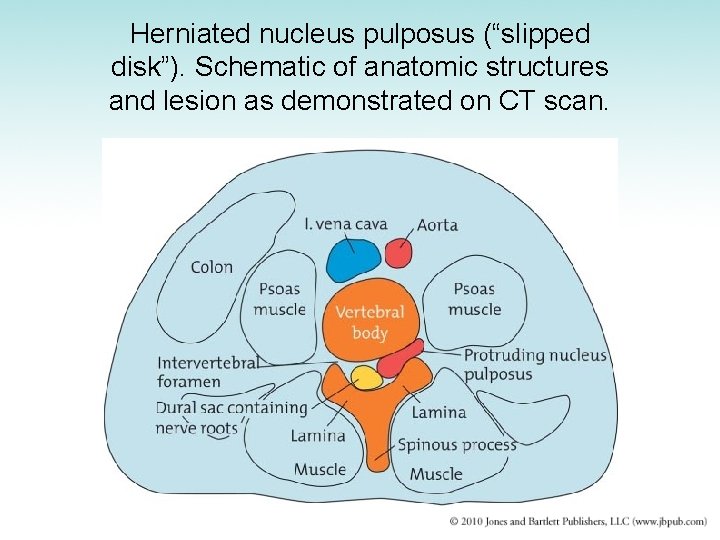

Intervertebral Disk Disease • Intervertebral disks undergo progressive wear -and-tear degeneration of both nucleus and annulus • Nucleus pulposus may be extruded through tear in annulus fibrosus • Manifestation – Sudden onset of back pain radiating down the leg • Diagnosis: CT scan or myelogram • Treatment: surgery

Herniated nucleus pulposus (“slipped disk”). Schematic of anatomic structures and lesion as demonstrated on CT scan.